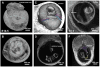

In this work, we report the use of iodine-contrast microCT to perform high-throughput 3D morphological analysis of mouse embryos and neonates between embryonic day 8.5 to postnatal day 3, with high spatial resolution up to 3µm/voxel. We show that mouse embryos at early stages can be imaged either within extra embryonic tissues such as the yolk sac or the decidua without physically disturbing the embryos. This method enables a full, undisturbed analysis of embryo turning, allantois development, vitelline vessels remodeling, yolk sac and early placenta development, which provides increased insights into early embryonic lethality in mutant lines. Moreover, these methods are inexpensive, simple to learn and do not require substantial processing time, making them ideal for high throughput analysis of mouse mutants with embryonic and early postnatal lethality.